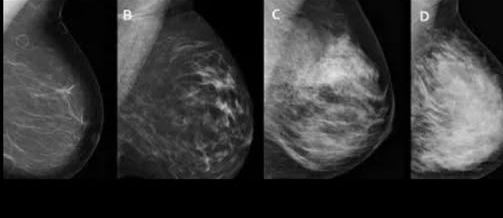

One key challenge with 2D mammography is that it can be difficult to spot cancer when a woman’s breast tissue is very dense.

“3D imaging takes not just one flat image but multiple images,” he says.

“It gives a much clearer depiction of the breast tissue and if a cancer is present.

“It really addresses the challenge with breast density. The work that we’ve done shows that 3D mammograms increase cancer detection for everyone regardless of breast density, but it particularly increases cancer detection in women with dense breasts.”